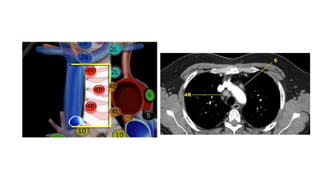

Localize within Mediastinum

Mediastinal Lines

Mediastinal Lymphadenopathy